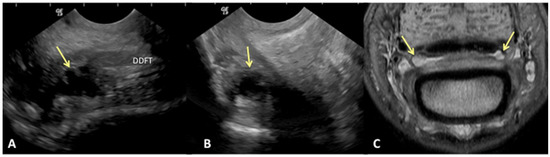

Results of sensitivity, specificity, and accuracy for comparisons of the findings of the DDFT, CSL, and navicular bursa are listed in Table 2. The low number of distal interphalangeal joint collateral ligament abnormalities resulted in low power for the statistic calculation, but prevalent findings are reported below. Ultrasound had the highest sensitivity for detecting enlargement and fiber damage of the dorsal aspect of the DDFT compared to identification of dorsal tearing of the DDFT on MRI, with a sensitivity of 85%, but it was less specific (60%) (Figure 1). Ultrasound was the least sensitive versus MRI to detect displacement (sensitivity 35%) of the CSL but was most specific for this finding (81%). Ultrasound also had a low sensitivity for detecting enlargement of the CSL (42%) but a specificity of 78% (Figure 2). Similarly, ultrasound was also less sensitive to detecting navicular bursa proliferation with a sensitivity of 47% but had higher specificity (78%) (Figure 3).

Figure 3. Transverse (A) and sagittal (B) ultrasound images of the lateral aspect of the proximal recess of the navicular bursa and corresponding transverse proton dense MR image (C). There is moderate cffusion and proliferation within the navicular bursa, identified on ultrasound and MRl (yellow arrows). (A) Lateral is on the left, palmar is on the top and dorsal on the bottom of the image. (B) Proximal is on the top of the image, distal is on the bottom. The palmar cortex of the middle phalanx is on the left of the image. (C). Palmar is on the top of the image, dorsal is on the bottom of the image.